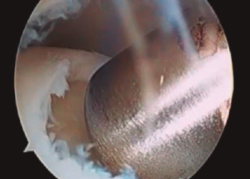

Figura 2. Técnica de estimulación medular con nanofracturas. Obsérvense los bordes del curetaje y la cruentación de la capa mineralizada.

- Posteriormente, realizamos la técnica de estimulación seleccionada entre: brocado o microperforaciones o nanoperforaciones. Preferimos realizar estas últimas a perforaciones más grandes que pueden dañar el hueso subcondral u otras técnicas de brocado con agujas de Kirschner que pueden producir necrosis inducida por el efecto térmico (Figura 2). Cada “nanofractura” debe realizarse separada 3-4 mm con una profundidad de 9-10 mm y un diámetro de 1 mm.